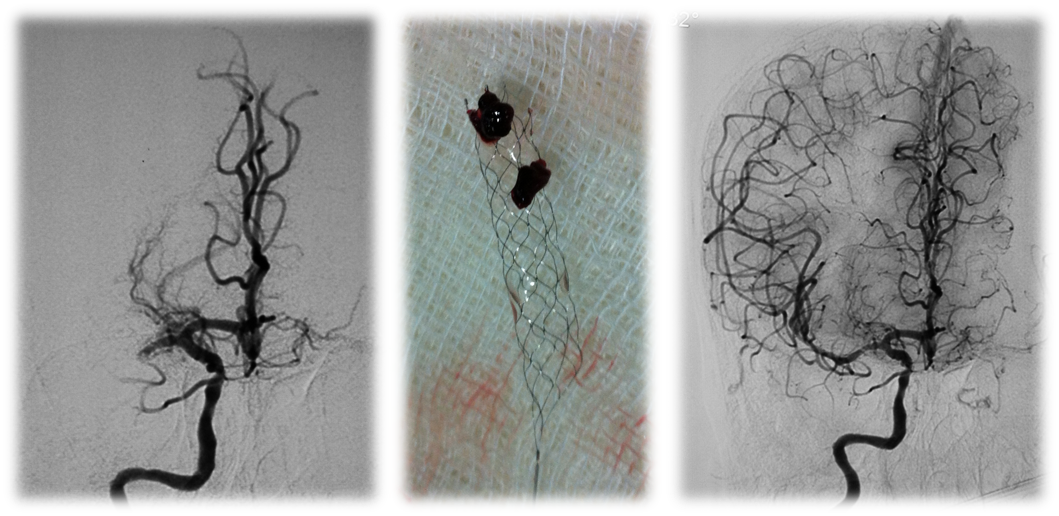

A term, appropriate-for-gestational-age neonate with normal APGAR scores and no history of perinatal hypoxia presented with seizures on day 2 of life.